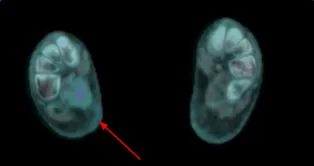

PET-CT DE CORPO INTEIRO PÓS-TRATAMENTO

ANÁLISE COMPARATIVA PET-CT DE CORPO INTEIRO PÓS-TRATAMENTO

Pré

Pós

- A IMPORTÂNCIA DO PET-CT NESTE CONTEXTO, JÁ QUE A LESĀO PRIMÁRIA NÃO TERIA SIDO VISTA POR COMPLETO E NEM AS SECUNDÁRIAS.